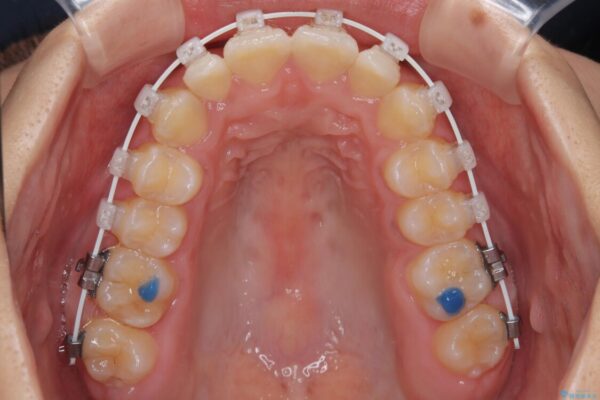

治療途中

• 目立ちにくい表側装置で1年完了!狭いアーチを側方拡大し前歯のデコボコを整えた症例 治療途中画像

・アーチを側方に拡大して歯が並ぶスペースを確保

・抜歯は避け、非抜歯での対応

・目立ちにくい審美装置による矯正